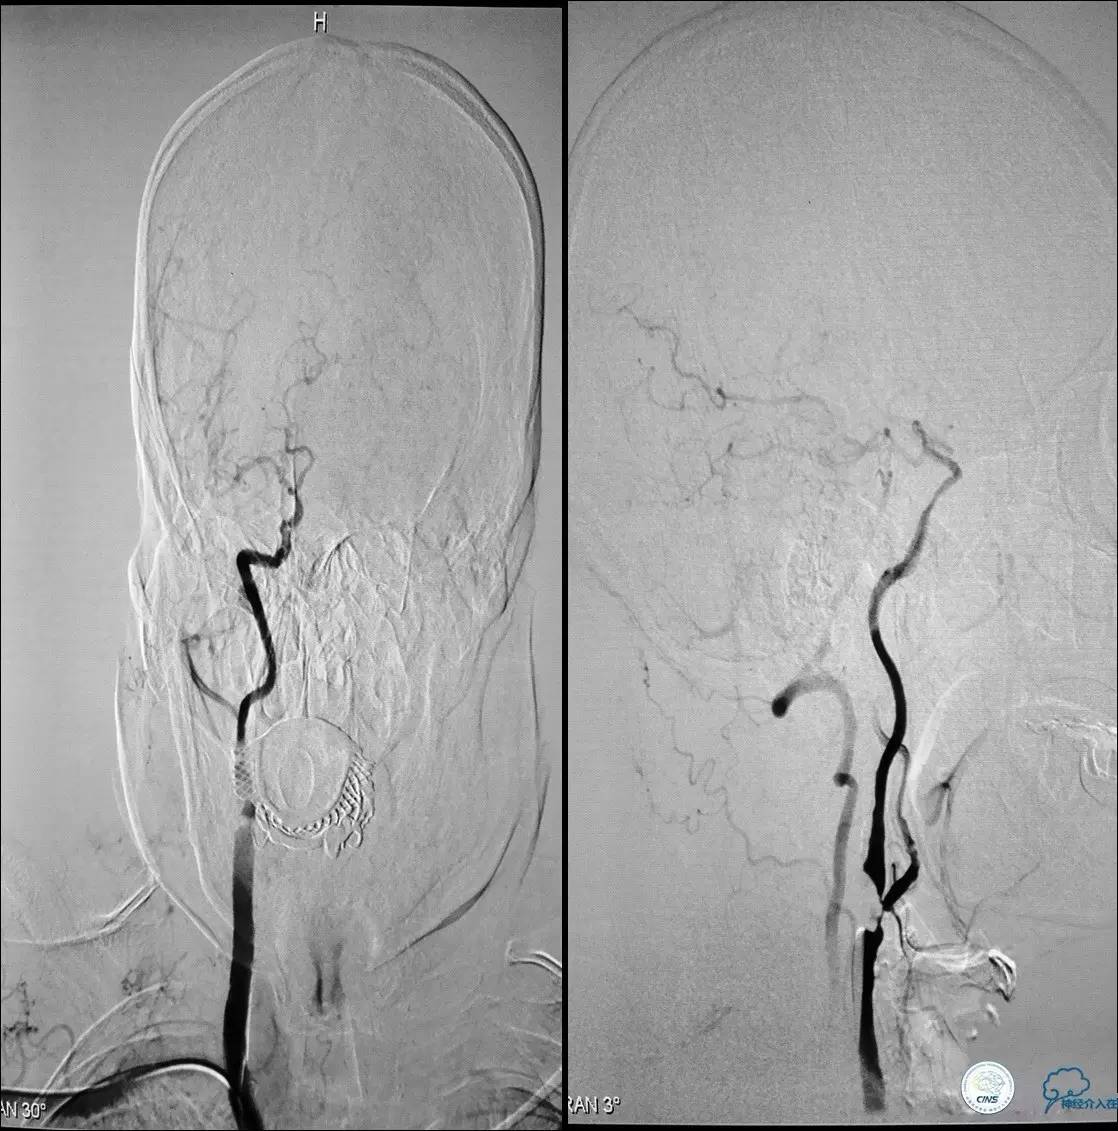

Case 1

》男,70岁。

》主诉:阵发性头晕伴视物模糊两月余。

》查体:右侧肌力V-级。

》既往史:高血压,糖尿病。

》辅助检查:颈动脉B超显示:左侧颈内动脉起始部狭窄 90%,右侧颈内动脉起始部80%。